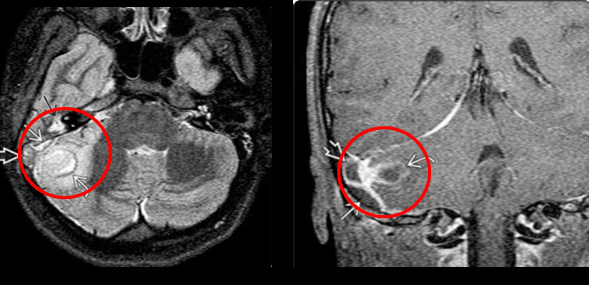

RM en otitis media

T1 - masa hipointensa en odio intenso

T2 - masa hiperintensa en odio y mastoides

RM en mastoiditis

Ver extensión intracraneal

T2- hiperseñal, disminución señal en seno sigmoide

Imagen en colesteatoma

Masa que destruye el hueso